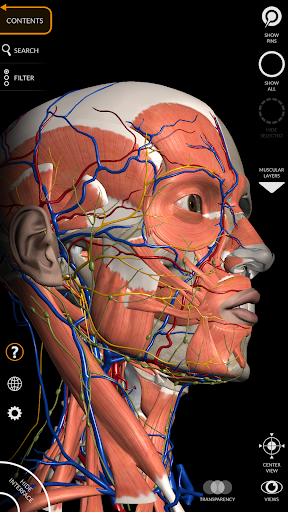

"Anatomy 3D Atlas" vous permet d'étudier l'anatomie humaine de manière simple et interactive.

Grâce à une interface simple et intuitive, il est possible d'observer chaque structure anatomique sous n'importe quel angle.

Les modèles anatomiques 3D sont particulièrement détaillés et avec des textures jusqu'à une résolution de 4k.

La subdivision par régions et les vues prédéfinies facilitent l'observation et l'étude de parties individuelles ou de groupes de systèmes et les relations entre différents organes.

• Système musculo-squelettique

• Système cardiovasculaire

• Système nerveux

• Faites pivoter et zoomez chaque modèle dans l'espace 3D

• Option pour masquer ou isoler un ou plusieurs modèles sélectionnés

• Filtrez pour masquer ou afficher chaque système

• Visualisation des muscles à travers des niveaux de couches depuis les plus superficielles jusqu'aux plus profondes